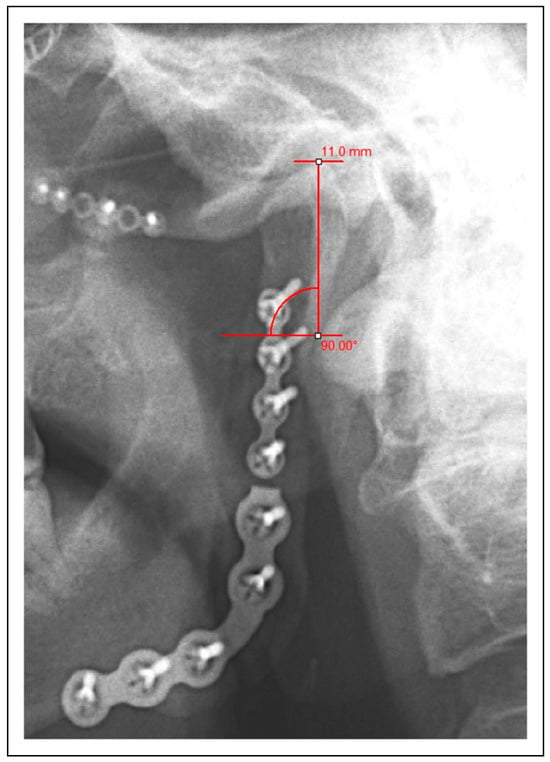

For each patient, clinical outcome measures and demographic data were collected from follow-up data including age at diagnosis, maximum interincisal opening (MIO), presence or absence of facial asymmetry, presence or absence of TMJ pain, presence or absence of malocclusion, incidence of post-operative infection, and need for further surgical intervention. Additionally, a comparison was made between baseline and follow-up imaging using panoramic radiographs to assess for radiographic evidence of condylar resorption in a vertical dimension for patients with appropriate post-operative imaging on record (n = 13). Per the exclusion criteria previously described, the baseline radiograph was taken post-operatively within 2 weeks of surgery and the follow-up radiograph was taken at least 6 weeks after surgery. These images were calibrated with MiPACS imaging software (Medicor Imaging, Charlotte, N.C.) using the diameter of a 2.0 mm screw head. The same screw head was used for both images in each patient. Then, using a technique previously described by J.M. Park et al., percent resorption of the condyle was calculated by comparing measurements of the vertical height of the condylar process between the two panoramic images. A horizontal line was drawn running tangential to the nadir of the sigmoid notch and measurements were then taken along a vertical line running perpendicular from this horizontal inferiorly to the apex of the condylar head superiorly (Figure 1) [18]. The degree of resorption was then calculated by dividing the difference between these measurements into the measurement for the first post-operative radiograph. All of the measurements were obtained by a single author (M.R.E.) using measurement tools available in the MiPACS imaging software. Resorption up to 25% of the condylar process was considered to be minimal and within the margin of error for the technique. Resorption between 26-50% was considered mild, 51-75% moderate, and 76-100% severe. A Pearson’s correlation coefficient (r) was calculated using Microsoft Excel for both age and length of follow-up as they relate to the degree of condylar resorption to better demonstrate the relationship of these variables.

Figure 1. Measurement of the condylar process on a postoperative panoramic radiograph using MiPACS imaging software. Calibration was performed using a 2.0 mm screw head. Measurements were taken from a horizontal line running tangential to the nadir of the sigmoid notch up to the apex of the condylar head along a perpendicular line.